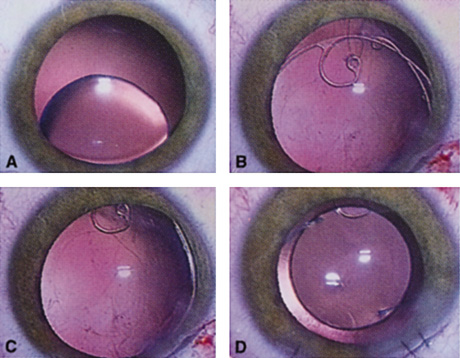

ENDOTHELIAL CELL COUNT.

Although slit-lamp examination can give the ophthalmologist an excellent estimate of endothelial health, sometimes a formal assessment of the corneal endothelial cell density is helpful (Fig. 4). This information is most likely to be helpful in advising patients who may be at greater risk of postoperative corneal decompensation. Specifically, patients with cornea guttata, previous ocular surgery, history of blunt ocular injury,56 exfoliation syndrome,57 iridocorneal-endothelial syndromes,58 or a history of glaucoma59 are known to have reduced endothelial cell counts. Patients with a history of acute angle closure are at particular risk because each episode of elevated intraocular pressure can damage endothelial cells.60

There are qualitative and quantitative methods for endothelial cell evaluation. Cell density can be measured directly with an endothelial cell camera. The surgeon also should view the photograph and qualitatively estimate the regularity of the endothelial cell mosaic. Some instruments calculate a coefficient of variability and percent of hexagonal cells.

When an endothelial cell camera is not available, qualitative assessment of count and cell morphology can be accomplished at the slit-lamp using a technique called specular reflection.61 The ophthalmologist focuses a narrow parallelepiped on the corneal epithelium, directing the beam at the periapical cornea from a 45-degree angle. The slit beam is moved slowly from side to side until the bright corneal reflex strikes the examiner's view from the epithelial surface reflection (first Purkinje-Sanson image). On high magnification, the examiner should focus on the endothelial surface just next to the bright reflex. The image of the endothelial mosaic will come into view. The surgeon can make a qualitative assessment of the cell density and degree of regularity. With practice, these estimates can be surprisingly accurate.

The implications of a reduced endothelial cell count are primarily prognostic and can provide the surgeon with more information to help counsel the patient about the risk of corneal decompensation with cataract surgery. Gentle phacoemulsification without triple procedure is recommended when cornea is clear and compact, given that a significant number of patients may be able to avoid a corneal transplant despite uncountable cell densities. However, these patients should be advised that they may be at an increased risk of requiring a corneal transplant.